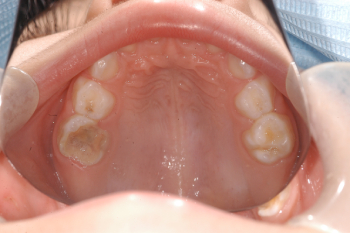

Odontopediatría

Caso 1